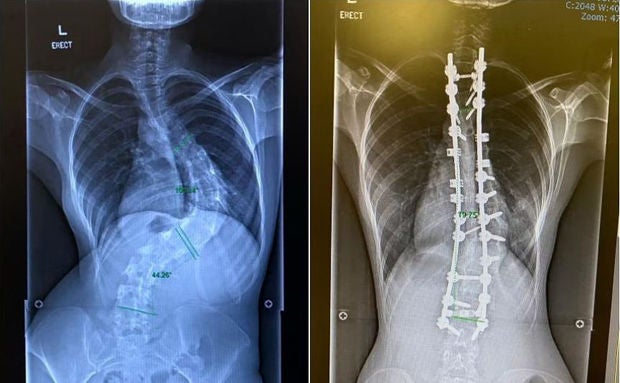

​To correct severe scoliosis (left), Ms Natasha Ramli had to have two titanium rods and 20 screws implanted in her back (right). PHOTOS: NATASHA RAMLI

“I was diagnosed at age 11 during one of those health screenings in primary school, and I was referred to a specialist. He recommended that I wear a body brace to correct my spine. That did not work out well and I stopped wearing the brace,” she told ST. Her scoliosis became progressively worse, measuring 80 degrees 10 years later. Surgical intervention is usually needed when the curvature exceeds angles of 45 to 50 degrees.

“I suffered back pains, developed uneven hips and had trouble breathing. When the surgeon discovered how severe the curve was, I was told to go for surgery if I wanted a good quality life,” she said. She had two titanium rods and 20 screws implanted in her back.